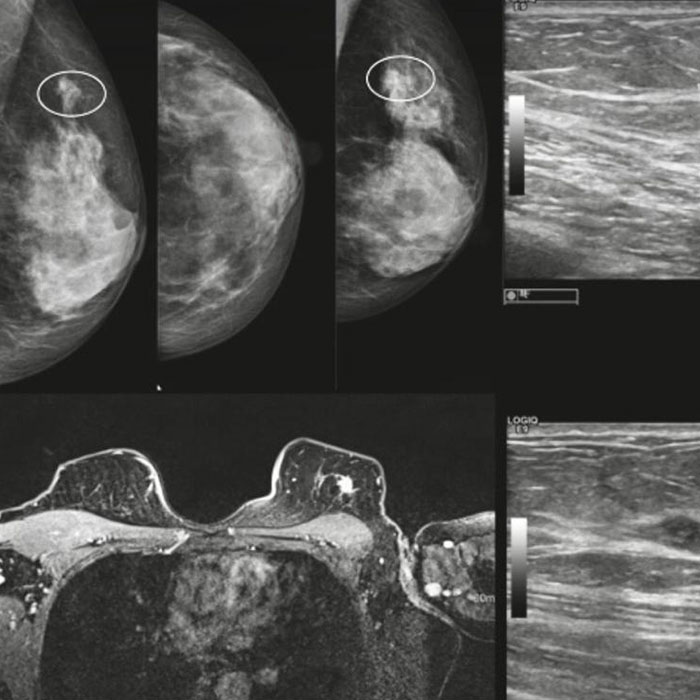

Hastanın öyküsü, yaşadığı rahatsızlık ve yapılacak operasyona bağlı olarak farklı yöntemler kullanılmaktadır. Meme radyolojisi doğrultusunda uygulanan yöntemler; mamografi, dijital mamografi, ultrasonografi, manyetik rezonans (MR), biyopsi, meme işaretlemedir. Uzman Hekim tarafından yapılacak kontroller sonrasında, hastanın durumu için en uygun olan yöntem belirlenerek bu yönde bir tedavi sunulmaktadır. Meme kanseri risk faktörü bulunan her kadın meme radyolojisi alanından destek alabilmektedir. Şüphesi olan ya da periyodik olarak kontrol yaptırmak isteyen ya da ailesinde meme kanseri öyküsü bulunan kadınlar, mevcut radyoloji hizmetlerinden yararlanarak ileri tetkik ve kontroller ile kansere karşı önceden önlem alabilmektedir.

Çoğu zaman genellikle mamografi çekilmesi ile tanı konulabilmektedir. Bu nedenle kadınların merkezimize başvuru yapması ile birlikte öncelikle bir hastalık öyküsü dinlenir ve ardından uygun görülen şekilde teşhis yapılmaktadır. Yapılacak kontroller sonucunda ise sonuçlar ve raporlar uzmanımız tarafından kapsamlı bir şekilde değerlendirecektir. Özellikle periyodik bir şekilde meme kanserine karşı önlem almak için meme muayenesi yaptıran kadınlar, kanser oluşumunun başladığı ilk anda durumun tespit edilmesine imkan tanır. Özellikle kanser gibi rahatsızlıklarda erken tanı kanserin yenilmesinde çok önemli olduğundan dolayı bu tip rahatsızlıklarda ve kontrollerde herhangi bir şekilde ihmale yer verilmemesi ve mutlaka uzman desteğinin alınması gerekir.